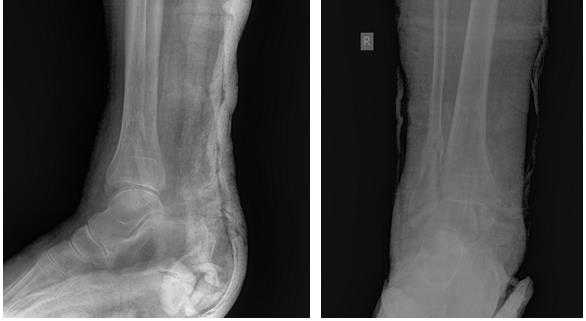

Клинический случай 1. Перелом обеих лодыжек с подвывихом стопы кнаружи.

44 В2-2

Пациентка Т. 80 лет. Травма за 3 недели до обращения, получила перелом обеих лодыжек правой голени со смещением, подвывихом стопы кнаружи. Обратилась в РТП, выполнена рентгенография, наложена гипсовая повязка. В связи с сохраняющимся выраженным отёком и болевым синдромом обратилась в клинику К+31.

На рентгенограммах в гипсе определяется значительный подвывих таранной кости кнаружи, консолидирующийся перелом нижней трети малоберцовой кости.